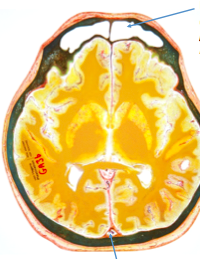

What sinus is shown?

what is its sensory innervation and how is this clinically relevant?

How does this help us to know level of positioning?

What sinus is shown posteriorly?

Frontal sinus

Sensory Innervation of the frontal sinus is the same as parts of the dura. Dura is innervated by different divisions of trigeminal (v1/v2/v3), frontal sinus is innervated by V1, therefore inflammation of the meninges can refer to the frontal sinus causing headache.

Aids positioning of the scan as frontal sinuses are within the frontal bone superior to the eyebrow.

Superior sagittal sinus is shown posteriorly, in attachment with the falx cerebri.

What lobes are shown?

What level is this scan at?

What fissure can be seen?

1) Frontal lobe

2) R temporal lobe

3) Occipital lobe

Fissure –> Sylvian or lateral fissure

Level of the scan must be at the level of the eyebrow region as the two frontal sinuses are shown.